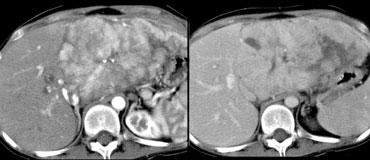

Trước tiên hãy quan sát các hình ảnh bên trái và cố gắng tìm các thuật ngữ mô tả phù hợp cho những gì bạn thấy. Sau đó tiếp tục đọc.

Tổn thương bên trái có các đặc điểm sau:

- Tổn thương giảm tỷ trọng ở thì động mạch và thì tĩnh mạch cửa, với ngấm thuốc ngoại vi.

- Tổn thương tăng tỷ trọng ở thì cân bằng, gợi ý mô xơ đặc.

- Tổn thương gây co rút bao gan.

Hình ảnh một khối thâm nhiễm kèm co rút bao gan và ngấm thuốc muộn kéo dài là đặc trưng điển hình của ung thư đường mật.

Ung thư đường mật thể thâm nhiễm không gây hiệu ứng choán chỗ, vì khi mô đệm trưởng thành, mô xơ sẽ co lại và gây co rút bao gan.

Không có nhiều loại u gây co rút bao gan, vì hầu hết các khối u thường gây phồng lồi bao gan.

Ca lâm sàng bên trái minh họa mức độ khó khăn trong việc phát hiện ung thư đường mật.

Chỉ trên các hình ảnh thì muộn, 8-10 phút sau tiêm thuốc cản quang, mới thấy được tổn thương tương đối tăng tỷ trọng. Đây chính là thành phần xơ của khối u.